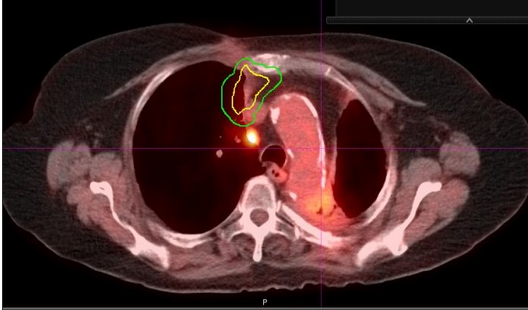

6年后,CT显示右上叶内侧有新发增强肿块,怀疑转移或新原发性肺癌(图2)。脑扫描显示转移疾病阴性。PET显示在预期区域有摄取和右肺门淋巴结有不确定的摄取(图3),但为阴性。 肺功能检查显示FEV1为1.45 L,为65%。 一氧化碳(DLCO)肺扩散能力为42%。 静息时饱和度正常,运动时下降至92%。

图2

图3